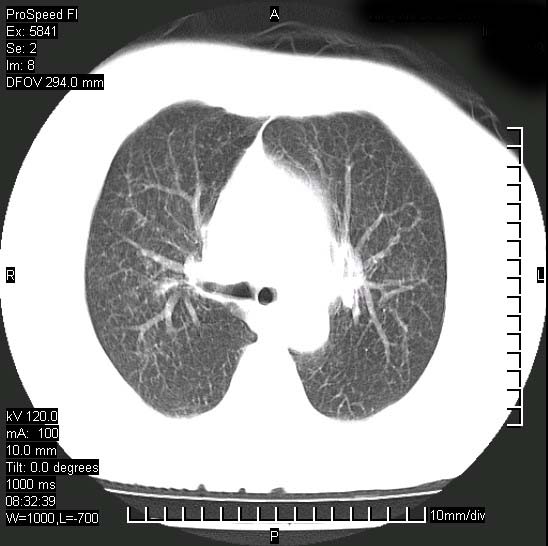

胸痛,咳嗽,气短一周,无发热。右上肺见一结节灶,边缘刺角,内见多个小钙化结节。考虑结核球?肿瘤? 余无异常没有上传。

胸膜是受侵的,考虑感染,结核球可能性大

考虑结核球,并胸膜局限性增厚!!